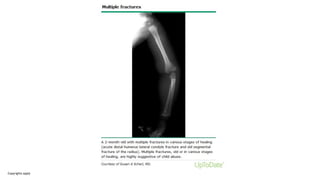

Fractures

• If a non-mobile infant has one or more fractures in the absence of a

medical condition that predisposes to fragile bones (for example,

osteogenesis imperfecta, osteopenia of prematurity)

• If x-ray have been undertaken

o Occult fractures (fractures identified on X-rays that were not clinically

evident) e.g. rib fractures in infants

o Fractures of different ages, showing different stages of healing

Copyrights apply